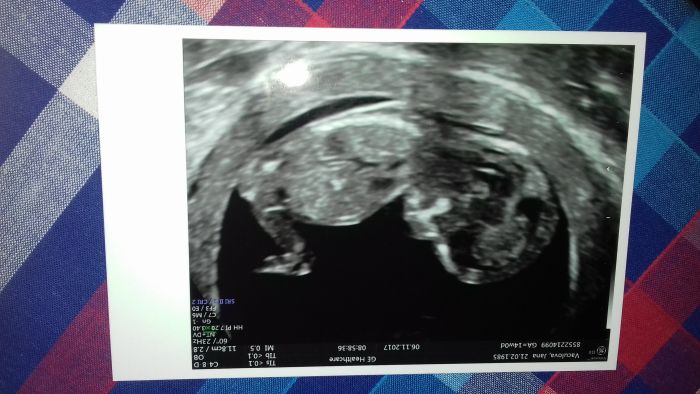

Autor: Jana V 6.11.2017 v 19:37

Ahojky holky tak sem dnes byla na screeningu v tom U.S.G. POL a úpravy spokojenost. Mela sem taky doktora hyjanka a vse nám vysvětlil. Prcek má 6.6 cm a je v pořádku a bude to s velkou pravděpodobností holcicka.Termín mam 14.5. Na mamciny narozeniny.platili sme sice 1400 a 100 ze tam se mnou byl pritel a 100 za fotku, ale sem spokojena. Na ten další scereenig jdu 4.1. V 19.45.ale nevadí mi to.

Jana V : krásná fotečka ;-) a slečna Jéé ;-) Kláro : taky jsem pro veliké rodiny akorád bych musela chodit někam krást už s jedním je to jak mít nový sporťak takže dve nám budou bohatě stačit ;-)

To ano Kami , ale byla sem hned na pojišťovně a 1000 korun mi proplati.Na te klinice me vzaly da se říct hned jak sem přišla (o pul hodiny dřív ☺).všichni byly prijemni tak se už těším az tam pojedeme zase.A sem jak sem měla byt dnes 13+0.